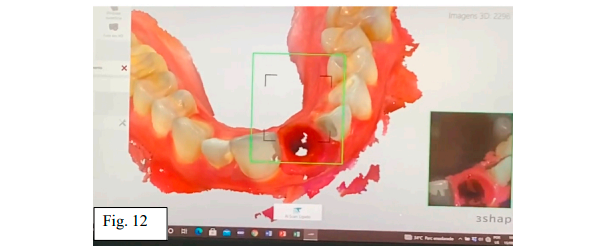

O escaneamento foi realizado com o scanner Trios 3 (3shape) tanto da posição do implante, quanto do perfil transmucoso obtido (Fig.12).